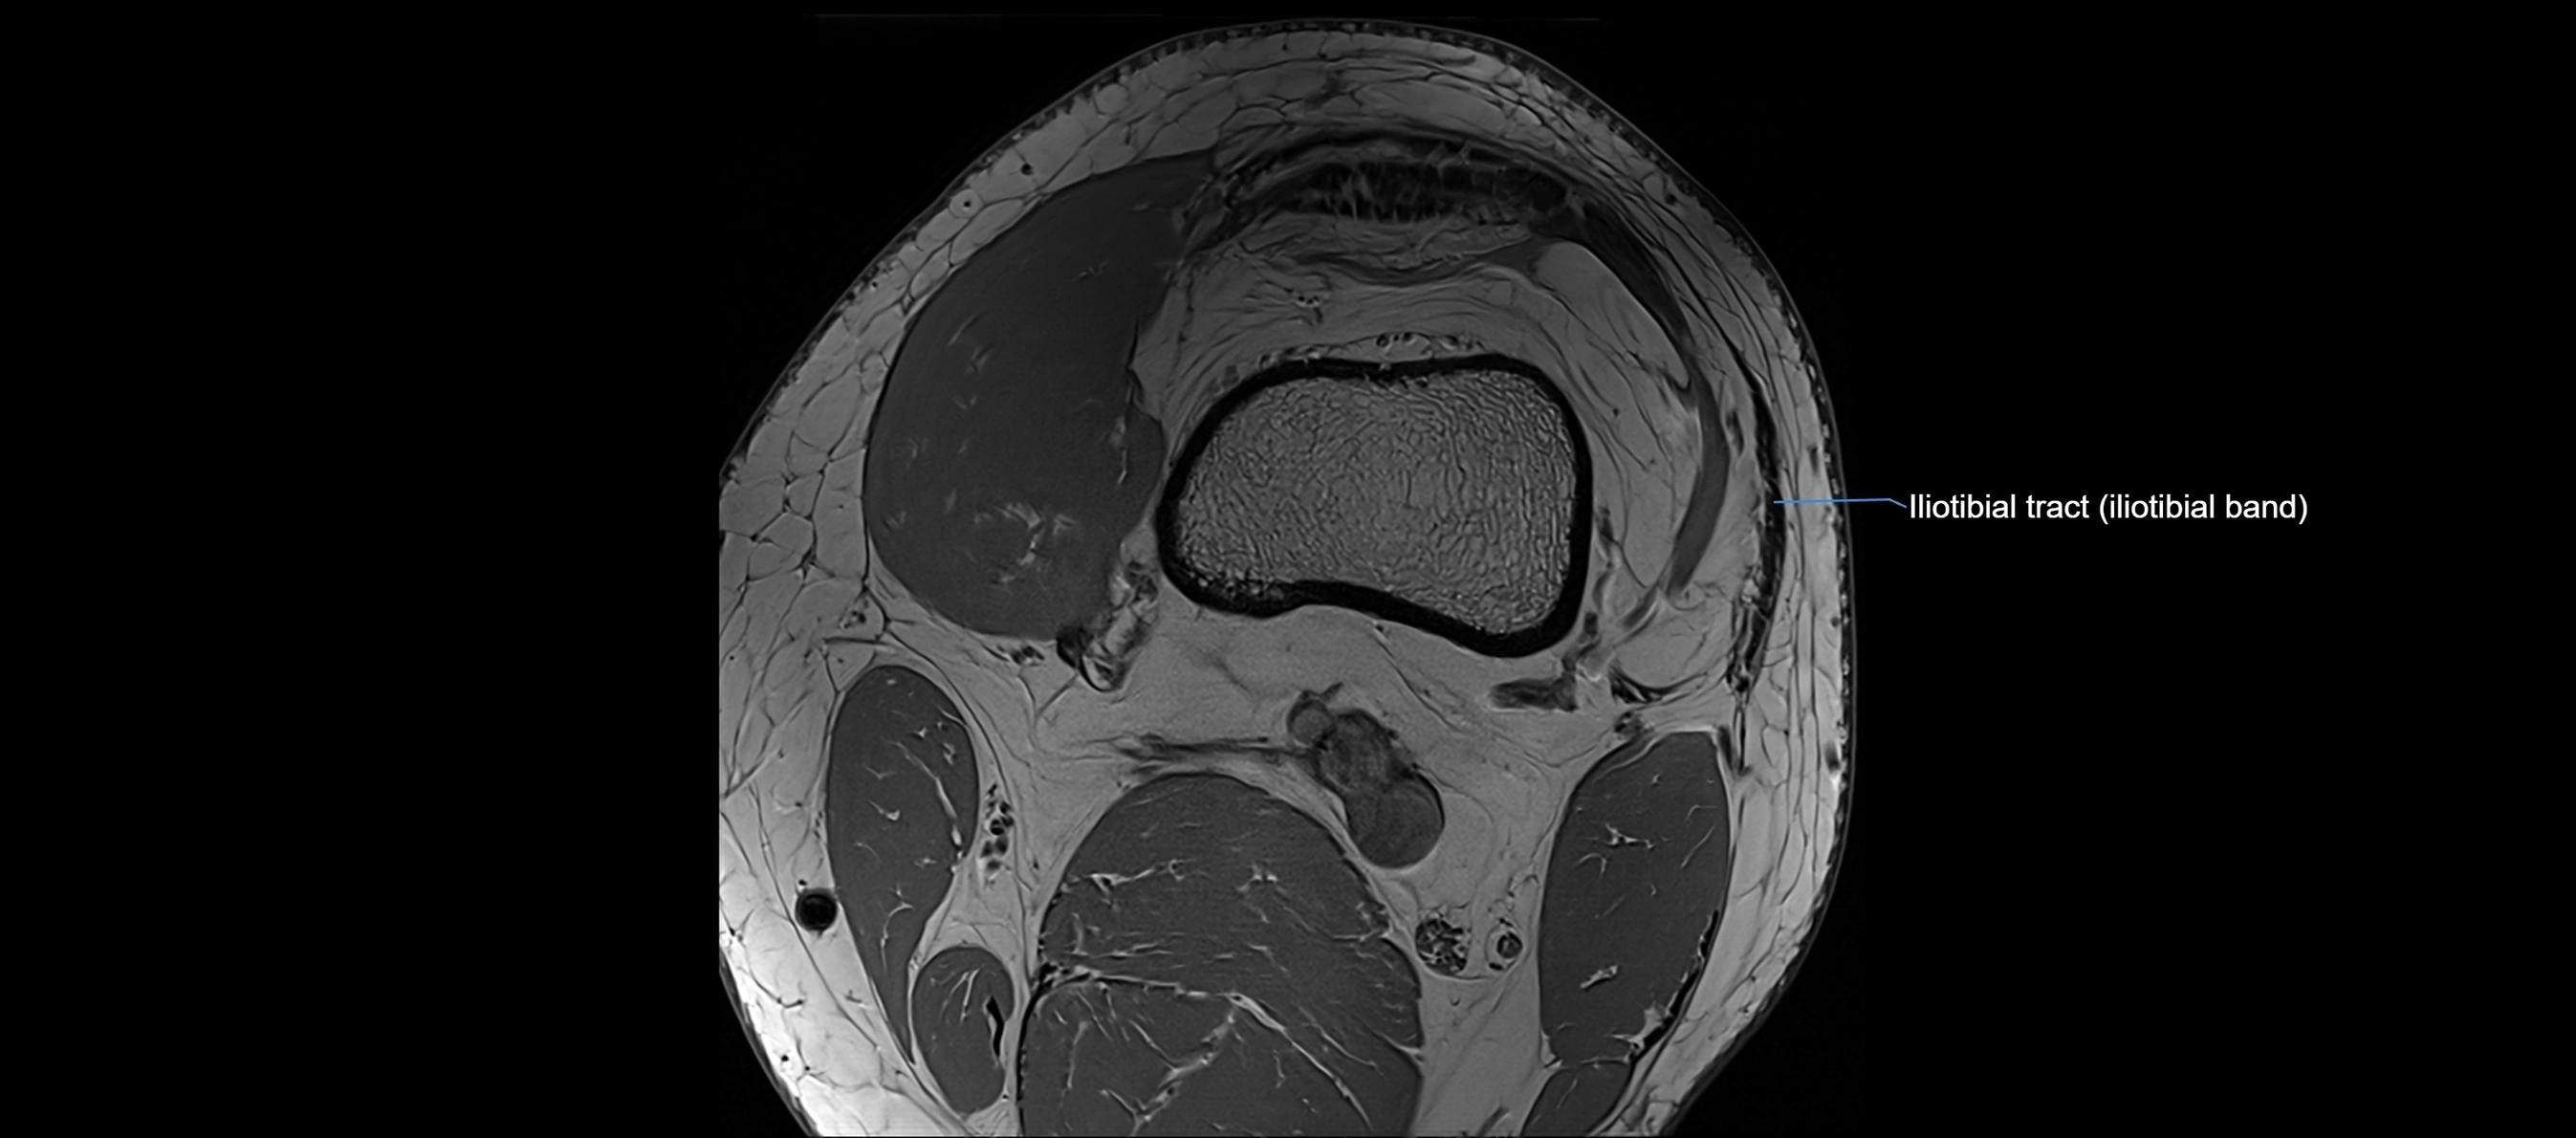

MRI images

image